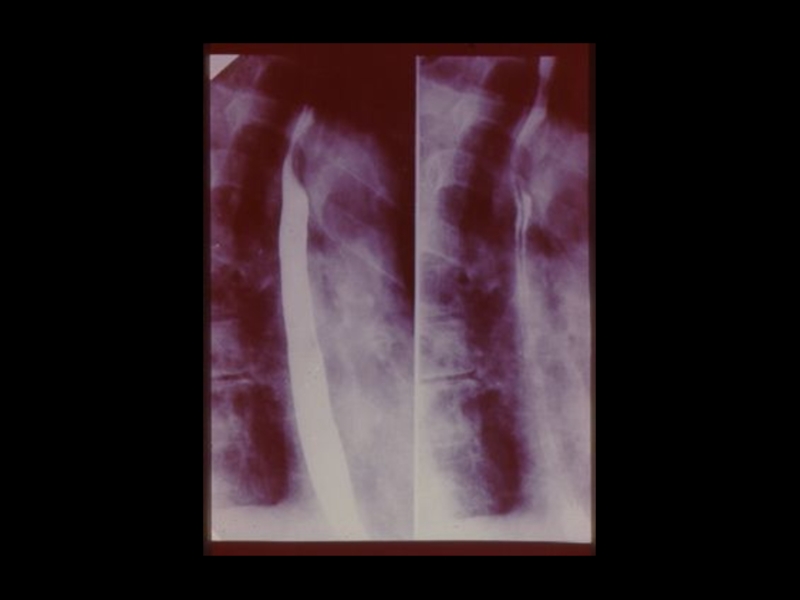

Слайд 18Методы традиционной рентгенодиагностики:

1. Общие методы

(рентгеноскопия, рентгенография)

2. Частные

методы

(флюорография, томография,

электрорентгенография, маммография и

другие)